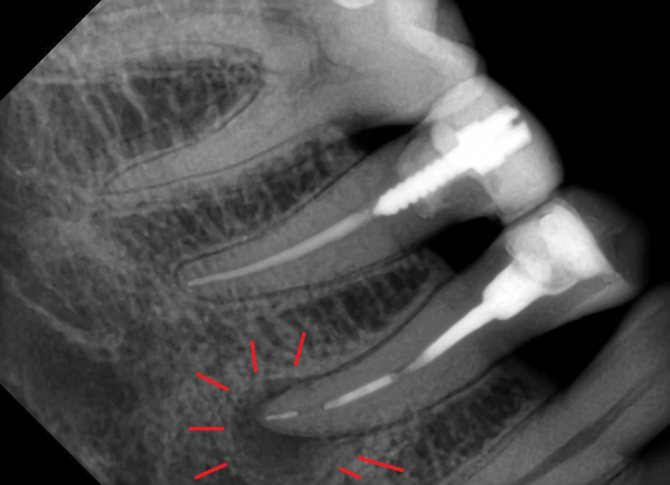

Размер патологического очага на 2D снимках иногда бывает обманчив.

На данном снимке видны изменения в верхнечелюстной пазухе.